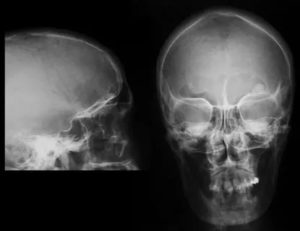

Остеомы имеют округлую форму с чёткими очертаниями. На рентген-снимке опухоль однородная, имеет широкую основу и гладкие поля. Крупные остеомы сдавливают мягкие ткани, вовлекая в патологический процесс мышцы и соединительную ткань. Всё это приводит к лицевой асимметрии с ухудшением мышечных функций.

- рентген-снимок лица и черепа в нескольких проекциях;

Информативным и предпочтительным методом исследования, помимо рентгена, является компьютерная томография.

К сожалению, выявление опухолей в зачаточной стадии сложно поддаётся ранней диагностике, поэтому проведение только рентген-снимка будет недостаточно и малоинформативно.

РГ ППН. Плотное образование в проекции правой лобной пазухи (остеома).

Рентгенографических изображений обычно достаточно для выявления патологии. При этом рентген точно показывает отсутствие разрушений близлежащих к новообразованию костей.

Рентген выявляет остеоидную форму: на изображении видно светлое округлое новообразование диаметром до сантиметра, окруженное плотным слоем костной ткани. Локализуется образование на поверхности кости или внутри ее.